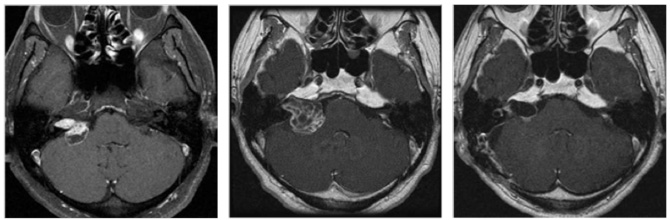

図3:50代男性 ガンマナイフ後3年半で拡大

(左図)ガンマナイフ時(中図)3年半後(右図)手術後 術後4年経過するも再増大なし